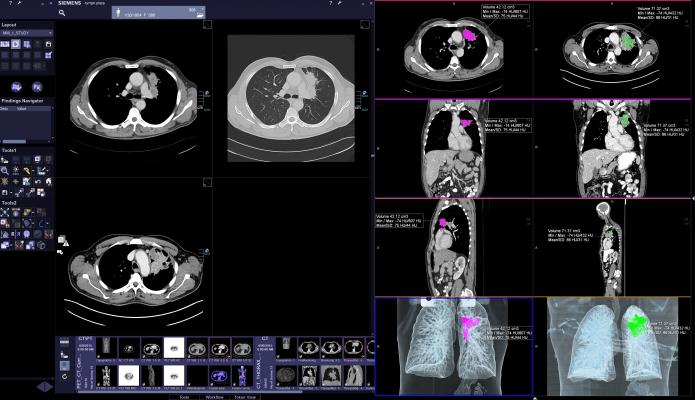

Siemens CT scanners also include a robust portfolio of imaging technologies that may help enable improvements when performing complex procedures such as lung biopsies. With Adaptive 3-D Intervention Suite, biopsy targets can be better visualized, which may aid physicians in minimally invasive procedures. Physicians can work more effectively by gaining access to nearly real-time guidance, while having a view of the whole organ and benefitting from automatic needle-detection algorithms and path planning tools.